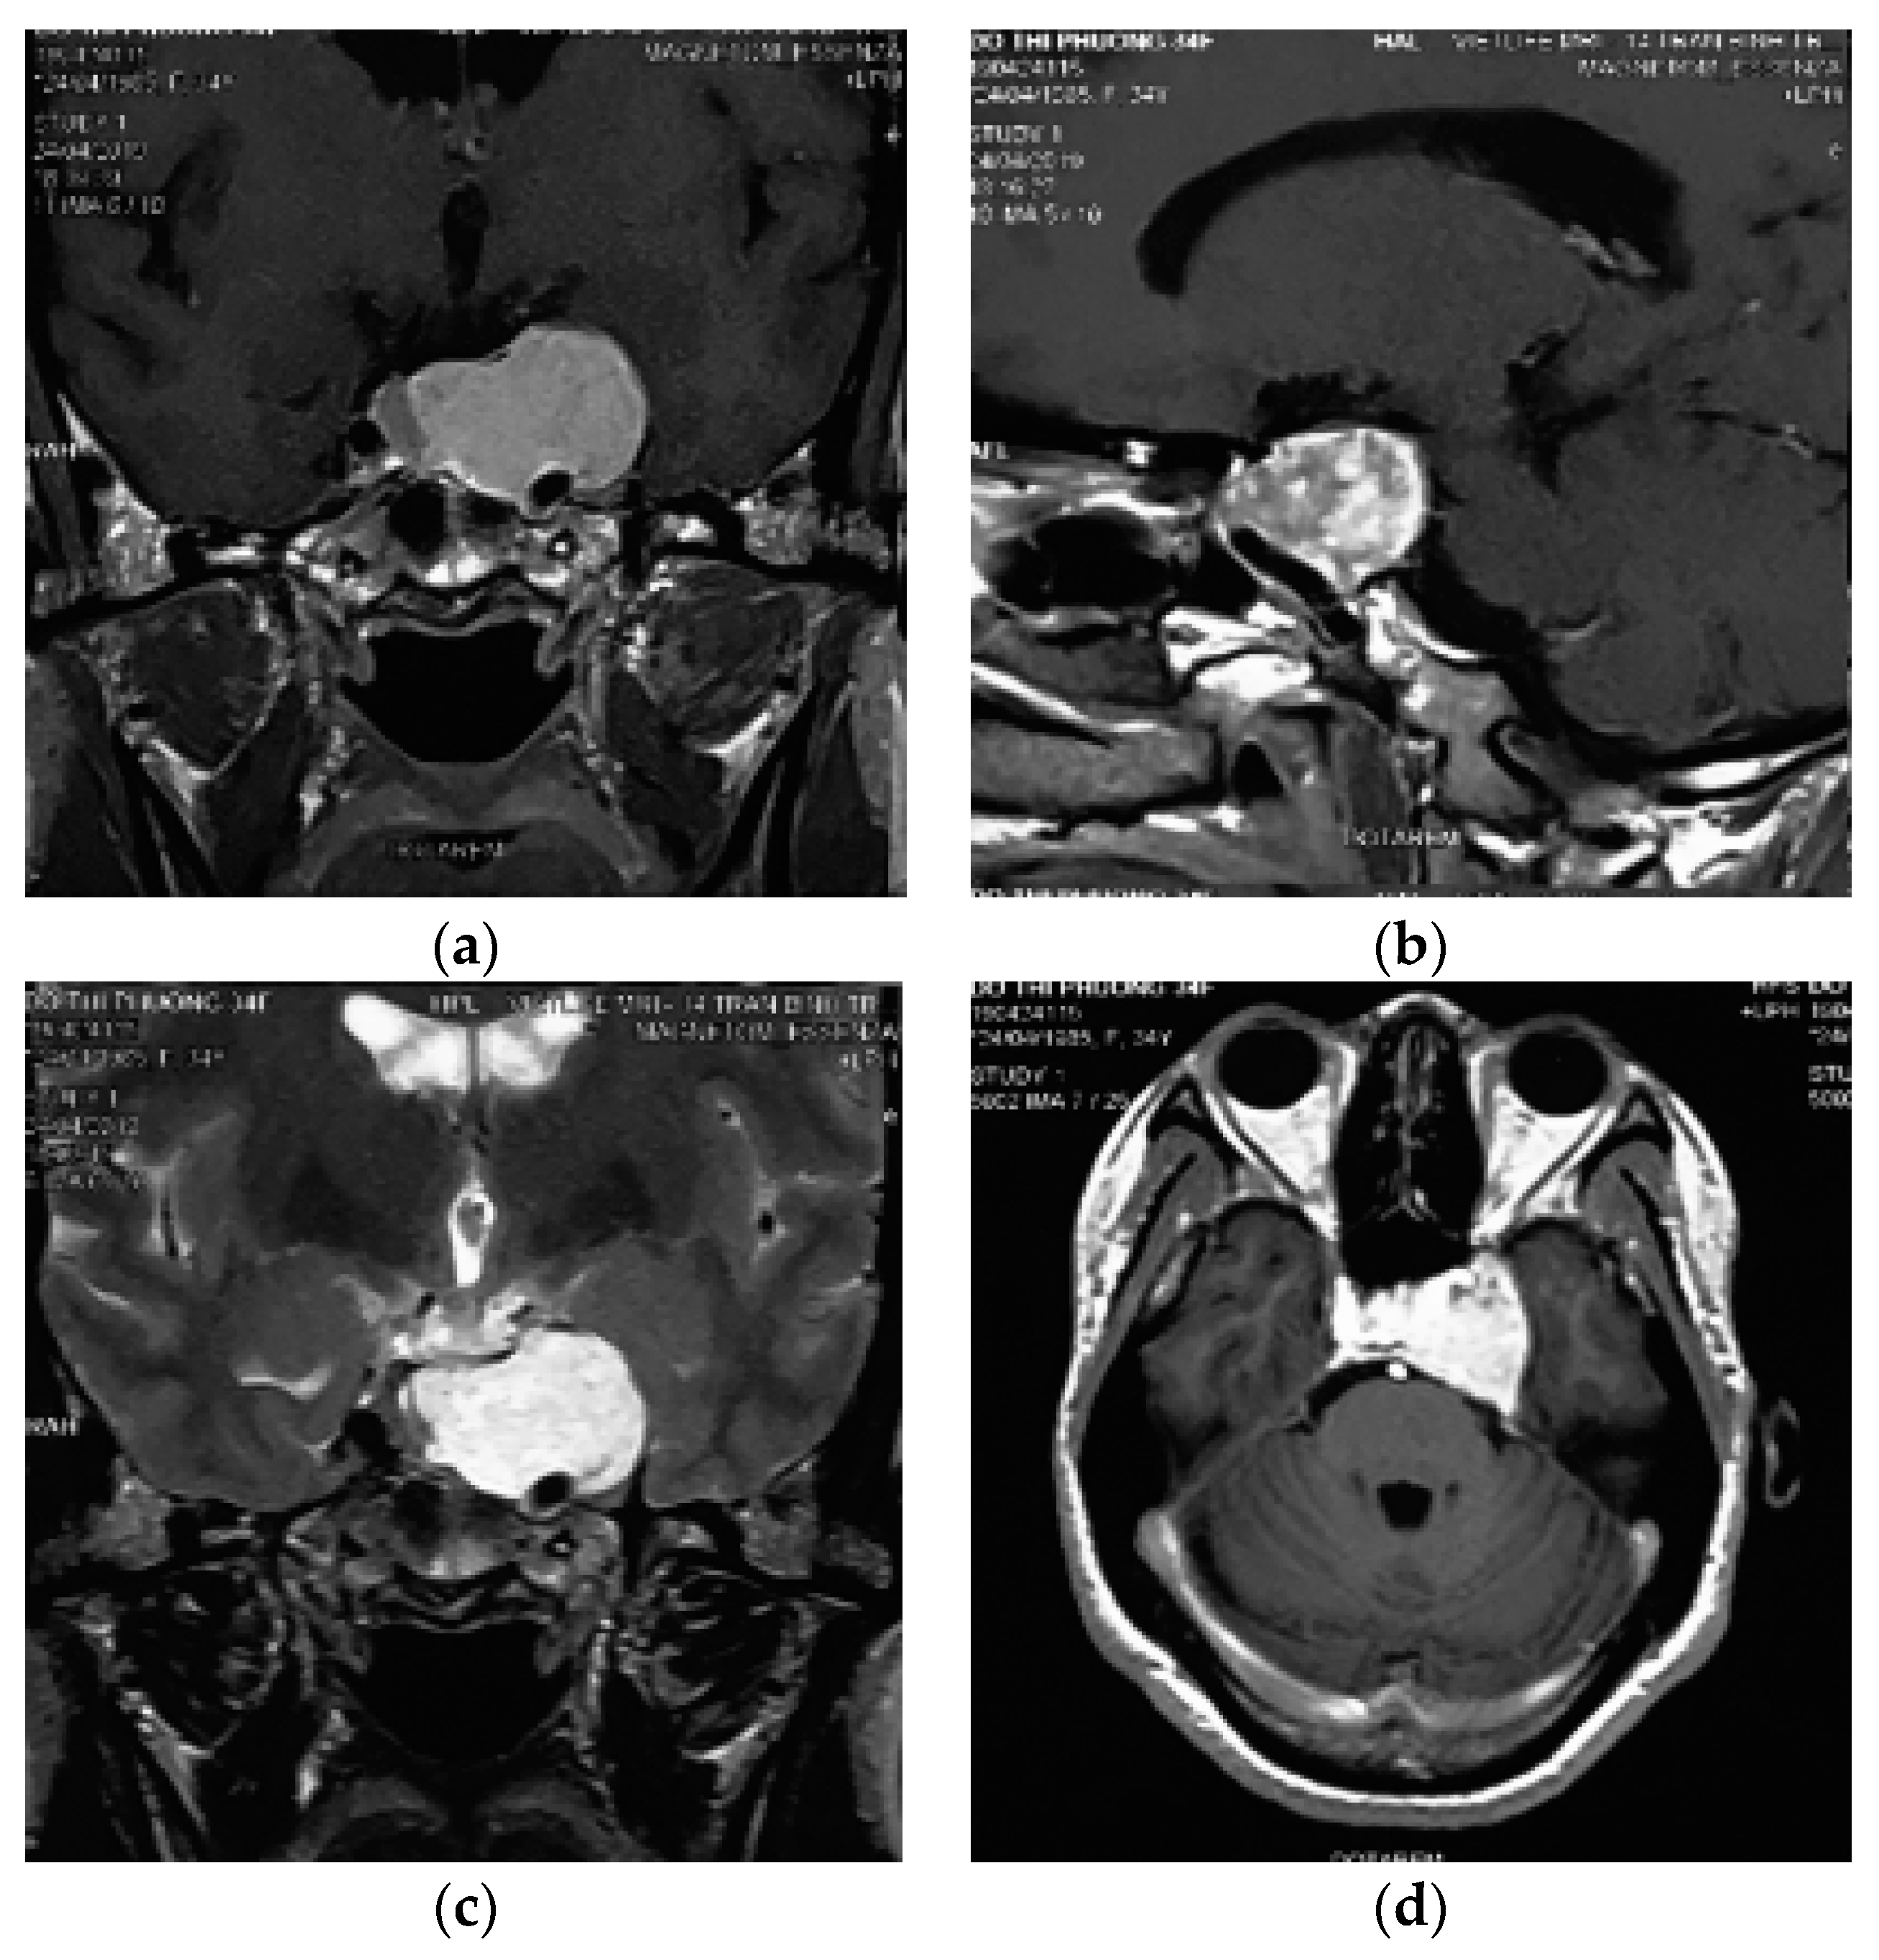

Histopathological examination of the mass revealed a cavernous haemangioma with many large cystically vessels filled by blood cells with an irregular thickness of the walls covered by benign flat endothelial cells (Figure 2). After surgery, the patient presented left ptosis, left eye exotropia (due to trauma of the third nerve), and left maxillary numbness (due to trauma of the V2 nerve) (Figure 3). However, the symptoms of third nerve palsy completely recovered after rehabilitation for 3 months. At the moment, the patient only has permanant numbness in the left cheek.

Figure 2.

Histopathology revealing large numbers of thin-walled vascular sinusoids, with a single layer of endothelium-lined capillaries, and scanty connective tissue. (a) H&E, 100×; (b) H&E, 250×. H&E, hematoxylin and eosin.